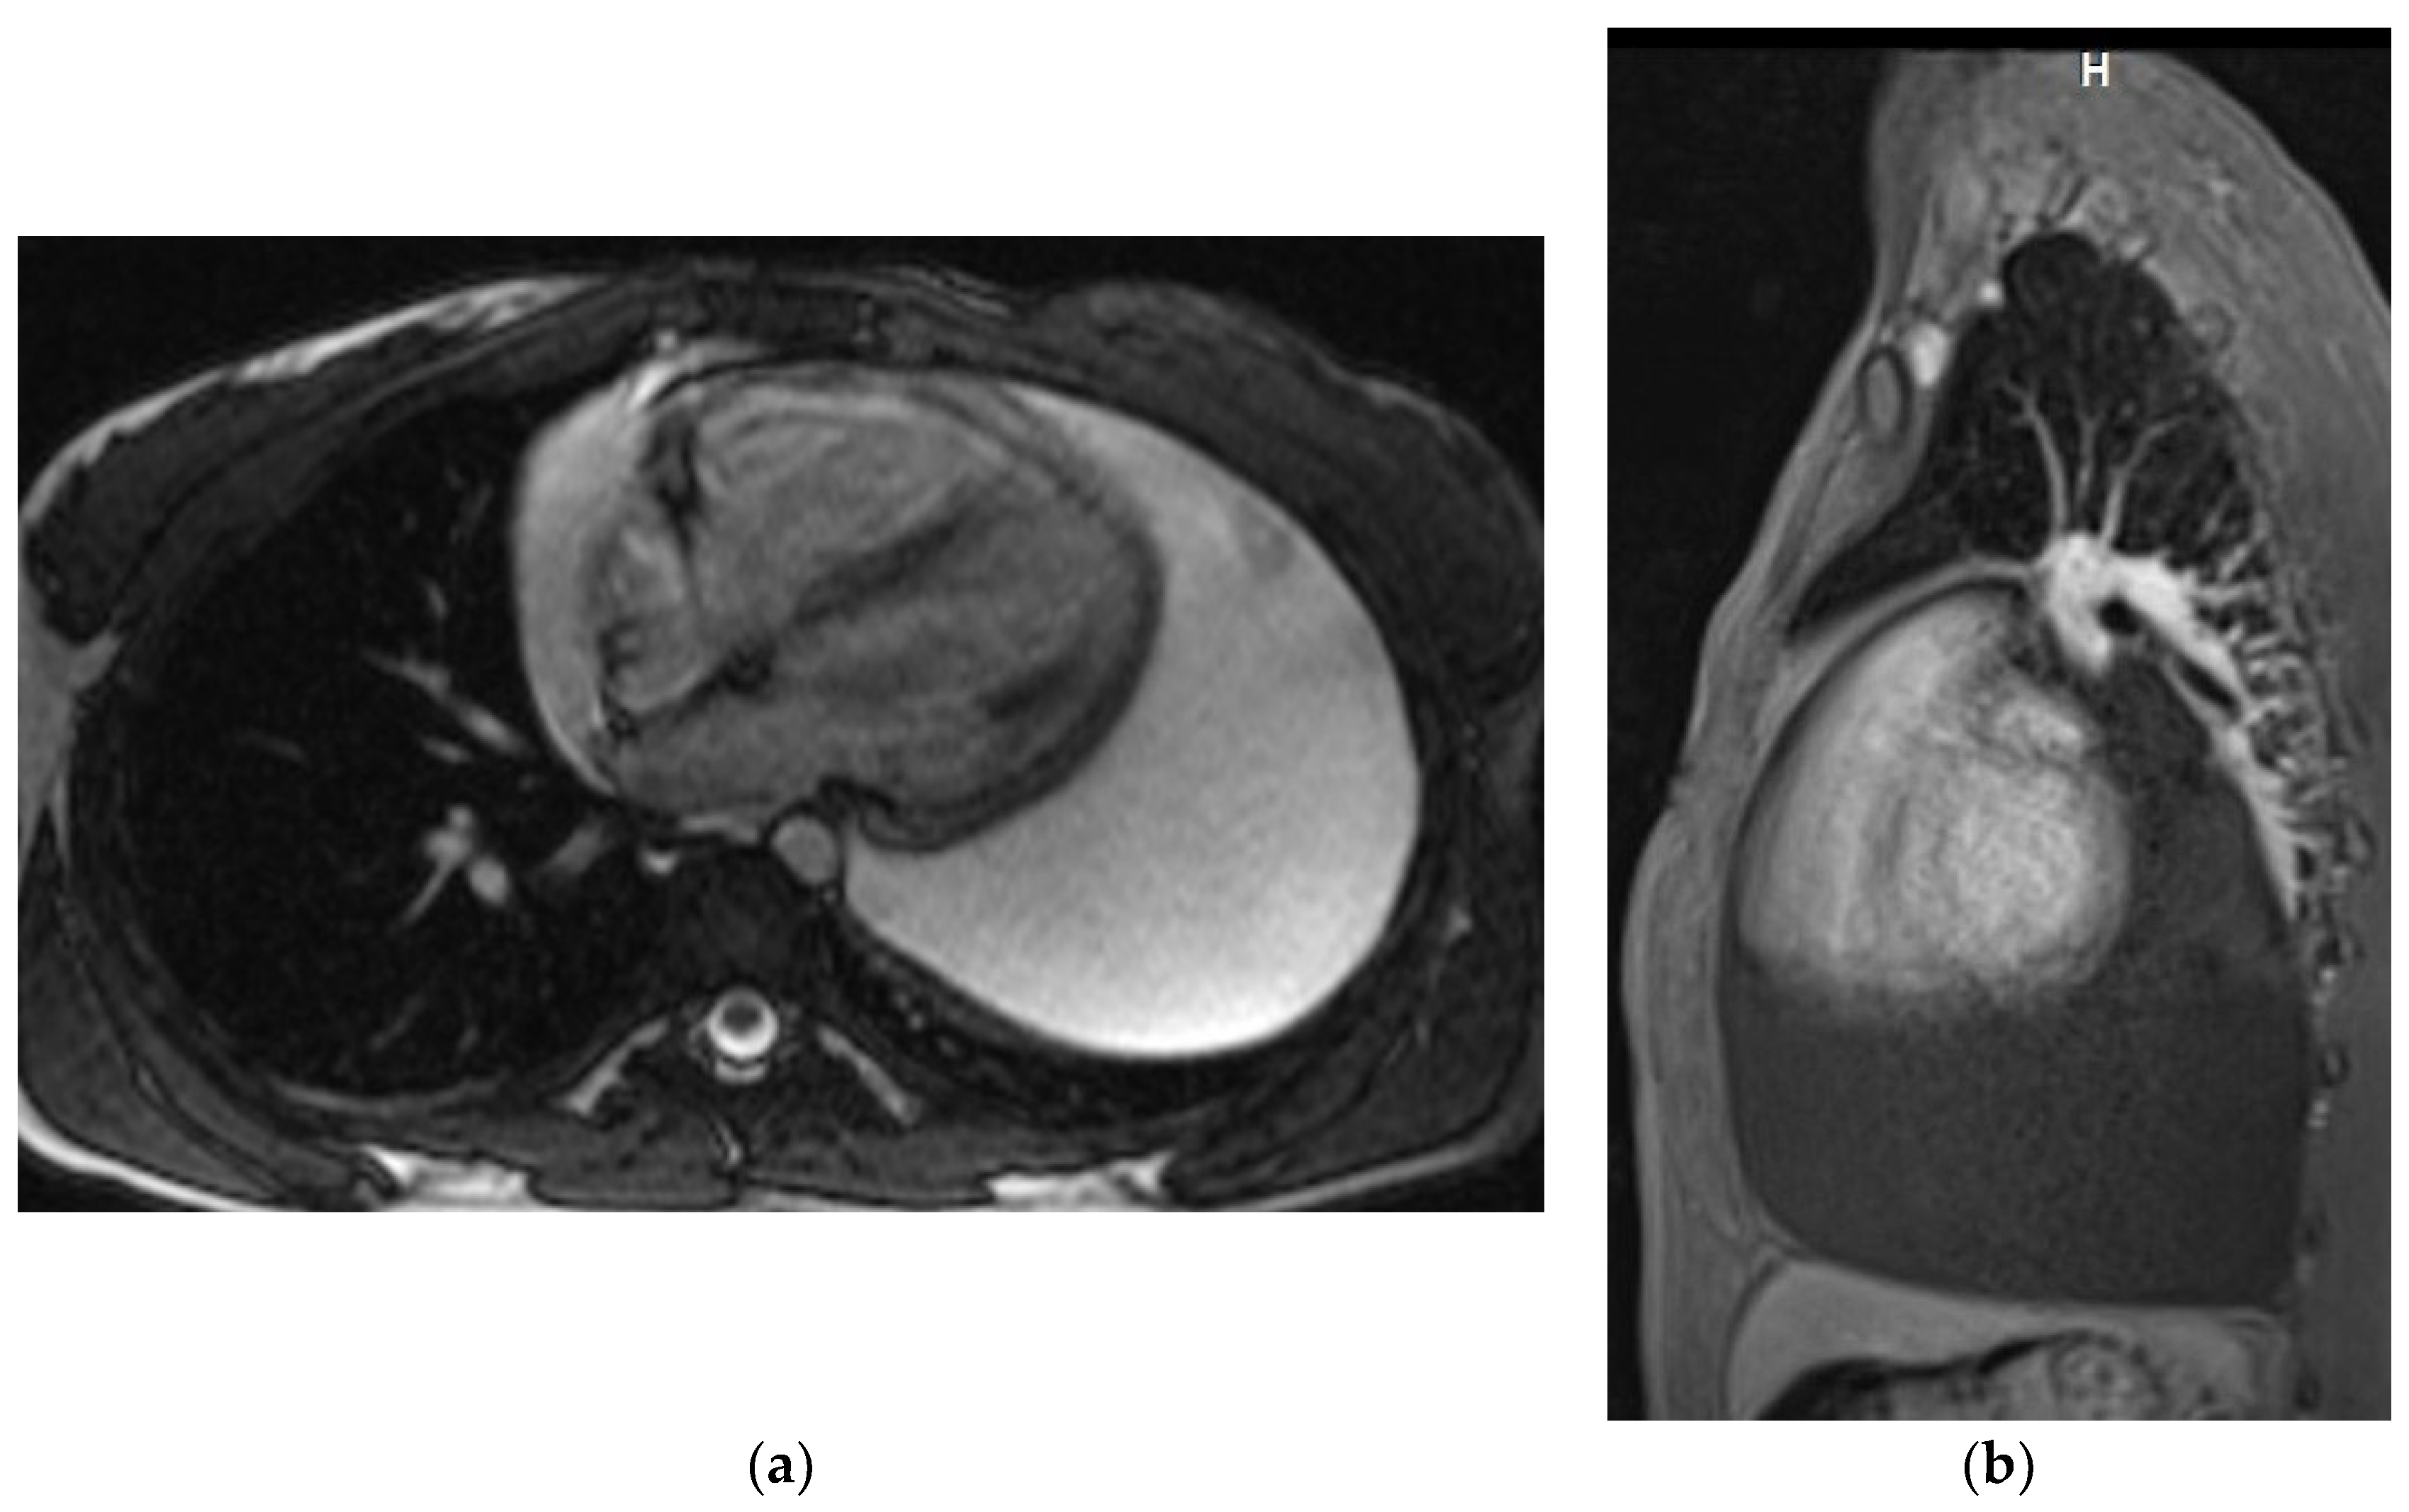

Chest MRI

Magnetic resonance examinations of the chest were performed by Siemens Avanto 1.5T scanner (Siemens, Munich, Germany). Routine MR sequences and ECG-gated sequences were used and T1-weighted and T2-weighted and fat saturation images were acquired. The examination was performed with gadolinium contrast agent administered through a double syringe system Optistar SF (Optistar, San Francisco, CA, USA) (Figure 3a,b).

Figure 3. Chest MRI. T2-weighted image, axial view (a) T1 weighted image with fat saturation and with contrast enhancement, sagittal view (b). Large pericardial effusion is seen, hyperintense on T2-weighted image (a) and hypointense on a T1-weighted image (b).